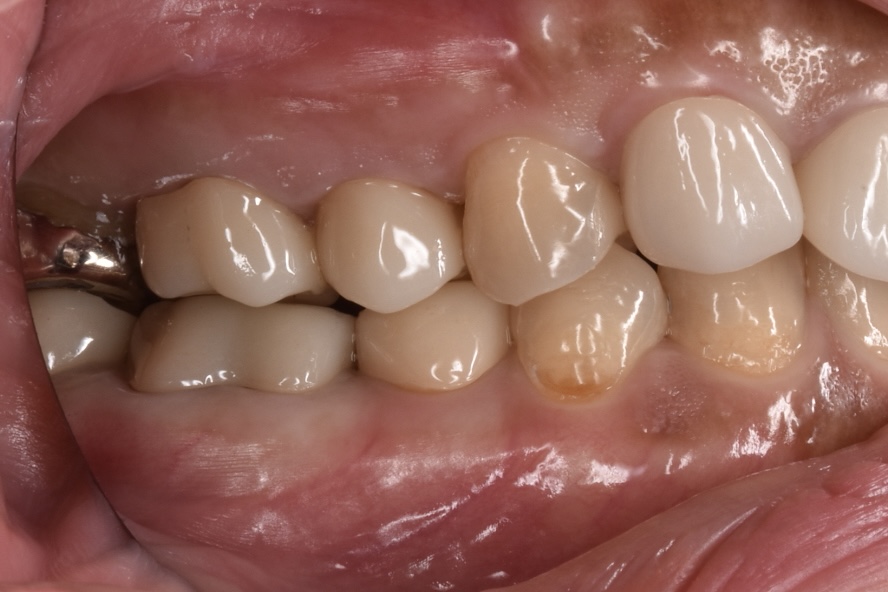

初回治療後より痛みがなくなり、とても快適に過ごせているとお言葉をいただきました。根管治療が奏功し炎症が引いているのが確認できたたため、最終的な治療を行い型取りを行いました。最終の修復はジルコニアクラウンです。

噛み合わせに関してもしっかり調整します。奥歯を比べてみると治療前の奥歯は平らなのがわかります。これでは噛むポイントが定まらず不安定な噛み合わせとなります。(*保険では過度な咬合にならないようにすること。割れたら2年以内なら無料で直せなどの制約があり出来るだけ噛ませないようにしてしまうのも理解できます。)なのでジルコニアでは歯にしっかり山と谷をつけて咬合を付与しています。